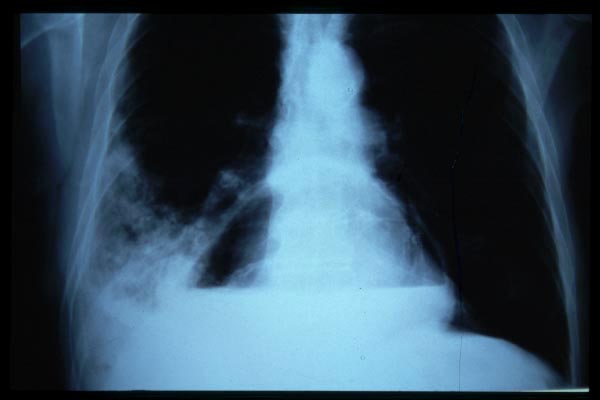

MO Distres respiratorio del adulto por trauma.